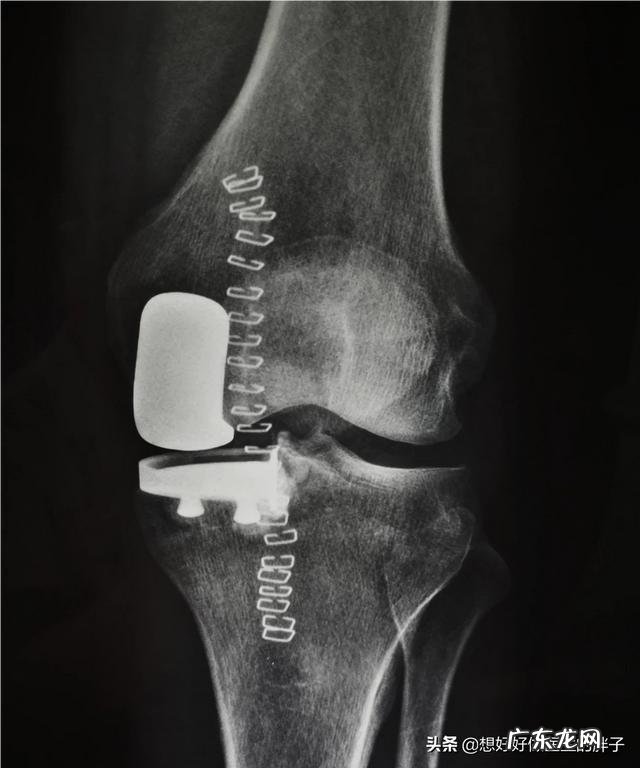

如果关节存在弹响,并且伴有关节的疼痛、肿胀以及不适,那么就要给予重视!导致病理性弹响多数发生在一些大关节,膝关节居多,究其原因有很多种,常见的会考虑到以下一些因素: